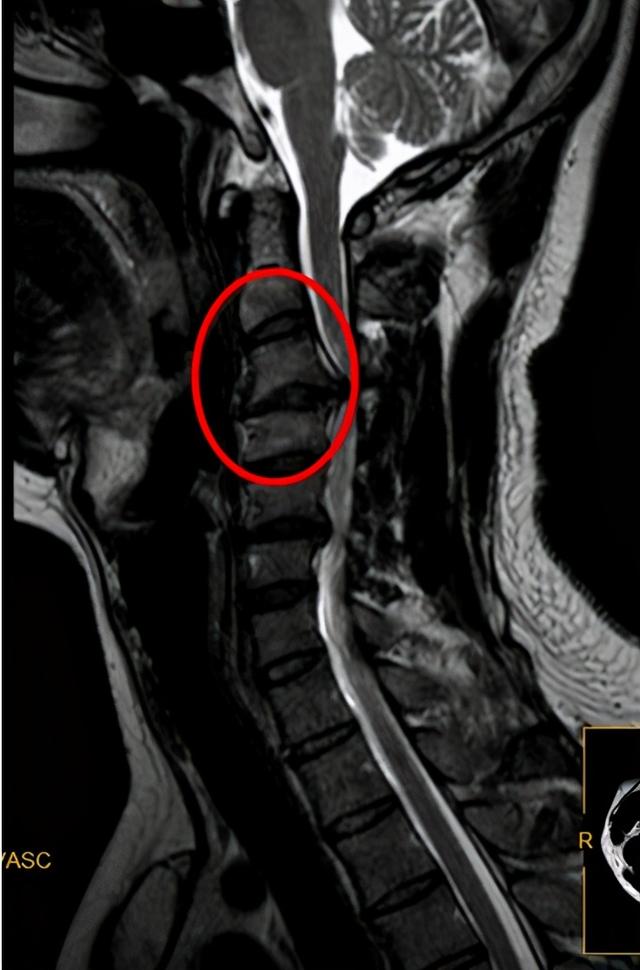

颈椎mri椎管狭窄,脊髓受压严重

磁共振提示颈椎多个间盘退变突出,颈4/5和6/7较严重.